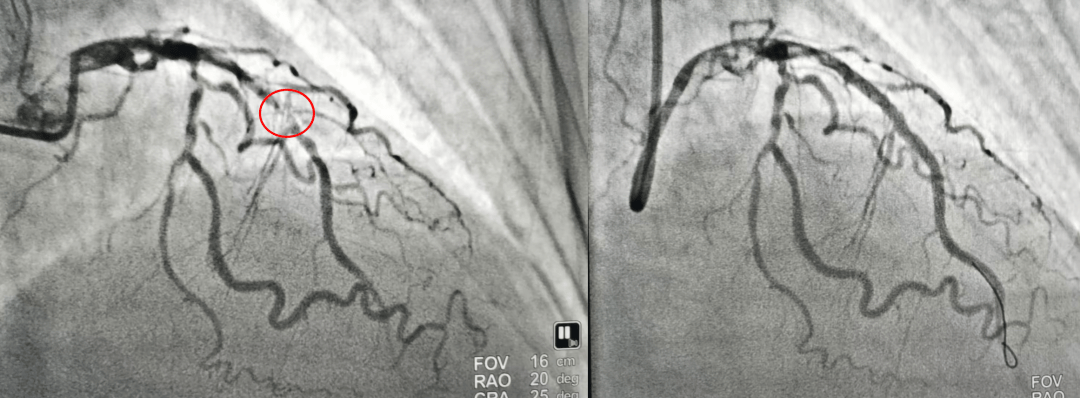

导管室内,穿刺、造影……患者心脏最重要的血管——前降支近中段次全闭塞,这是导致其大面积心肌梗死的“元凶”。团队沉着冷静,凭借精湛的技术,迅速通过导丝、球囊扩张,并成功植入一枚支架。随着支架的释放,堵塞的血管恢复畅通,血流得以重新灌注心肌,手术顺利完成。